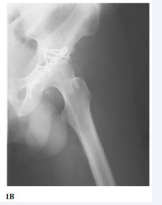

A 60 years old female patient underwent, in our clinic, a primary total hip replacement (THA) with a protrusion cage with screws and cemented cup, because of insufficient acetabular bone stock. The patient had a successful post-operative recovery. One month post-surgery, she started complaining for sciatica, with moderate pain and progressive difficulty while walking and she visited orthopedic surgeons in her living town. She finally returned to our clinic ten months after the primary THA with drop foot and electromyography findings indicating pressure of the peroneal nerve at the level of the operated hip joint. The x-ray documented a vertically positioned protrusion cage with its lower part not anchored to the sciatic bone (Figures 2A,2B).

Figure 2: Anteroposterior (A) and lateral (B) x-ray of total hip replacement with protrusion cup vertically positioned. Notice that the lower part of the cage is not in contact to the underlying sciatic bone (pointed with black arrow), laying inside the muscles.

The patient was subjected to an acetabular cup revision surgery using a Muller ring with screws and cemented cup. During the operation, sciatic nerve was found uncut but edematous surrounded by inflamed scar tissue behind the lower part of the cage which initially was not anchored close to sciatic bone. After the removal of the cage the nerve was carefully dissected and all scar tissues were removed. The new acetabular prosthesis was implanted and the nerve was double checked and embedded in a secure soft tissue envelope. The postoperative period was uneventful. Ten months post operation, the patient still usesthe drop foot splint (without any motor improvement) but she reports that the sciatica pain has significantly decreased (more than 50% according to pre and postoperative measurements of Visual Analogue Scale scores).